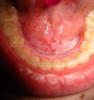

Vikki Опубликовано 29 мая, 2010 Поделиться Опубликовано 29 мая, 2010 вот такое вот появилось во рту, что это может быть и как это лечить? не болит, не опухает. вообще никаких признаков что оно там есть кроме ребристой поверхности. совсем нет времени сходить к специалисту( Ссылка на комментарий

Vikki Опубликовано 31 мая, 2010 Автор Поделиться Опубликовано 31 мая, 2010 Здравствуйте!Скажите,сколько времени присутствуют эти изменения в полости рта,причиняют ли они вам дискомфорт и есть ли у вас привычка или же необходимость держания во рту сторонних предметов,напр.(рассасывание таблеток)? ой ну не знаю. ну с этого года это точно. наверное с марта. вообще никаких беспокойств абсолютно, таблетки не употребляю, так же как и жвачки. есть пирсинг языка, но он уже 6 лет и серьга не касается этого места. сначала на нее подумала, заменила мед сталь на пластик, ждала может пройдет, но прошел уже месяц не проходит. Ссылка на комментарий

Медея хт Опубликовано 31 мая, 2010 Поделиться Опубликовано 31 мая, 2010 ой ну не знаю. ну с этого года это точно. наверное с марта. вообще никаких беспокойств абсолютно, таблетки не употребляю, так же как и жвачки. есть пирсинг языка, но он уже 6 лет и серьга не касается этого места. сначала на нее подумала, заменила мед сталь на пластик, ждала может пройдет, но прошел уже месяц не проходит.Большая вероятность того,что у Вас лейкоплакия.Если уберете причину раздражения дна полости рта,то после курса кератопластиков все пройдет.Думаю,что причиной может выступать,все-таки,серьга.Обязательно оьратитесь к врачу,так как постоянное травмирование может привести к онкопатологии.Удачи Вам! Ссылка на комментарий

Никсон Опубликовано 1 июня, 2010 Поделиться Опубликовано 1 июня, 2010 ой ну не знаю. ну с этого года это точно. наверное с марта. вообще никаких беспокойств абсолютно, таблетки не употребляю, так же как и жвачки. есть пирсинг языка, но он уже 6 лет и серьга не касается этого места. сначала на нее подумала, заменила мед сталь на пластик, ждала может пройдет, но прошел уже месяц не проходит. Если допустить, что это лейкоплакия, то Вам необходимо обратиться к специалисту по заболевания слизистой оболочки. Вы не можете объяснить причину возникновения этой белой бляшки( плака) в области слизистой оболочки, этот плак Вы не можете стереть, убрать, как я понял.Это позволяет предположить лейкоплакию. Все "белые" поражения этой категории требуют проведения биопсии. Ссылка на комментарий